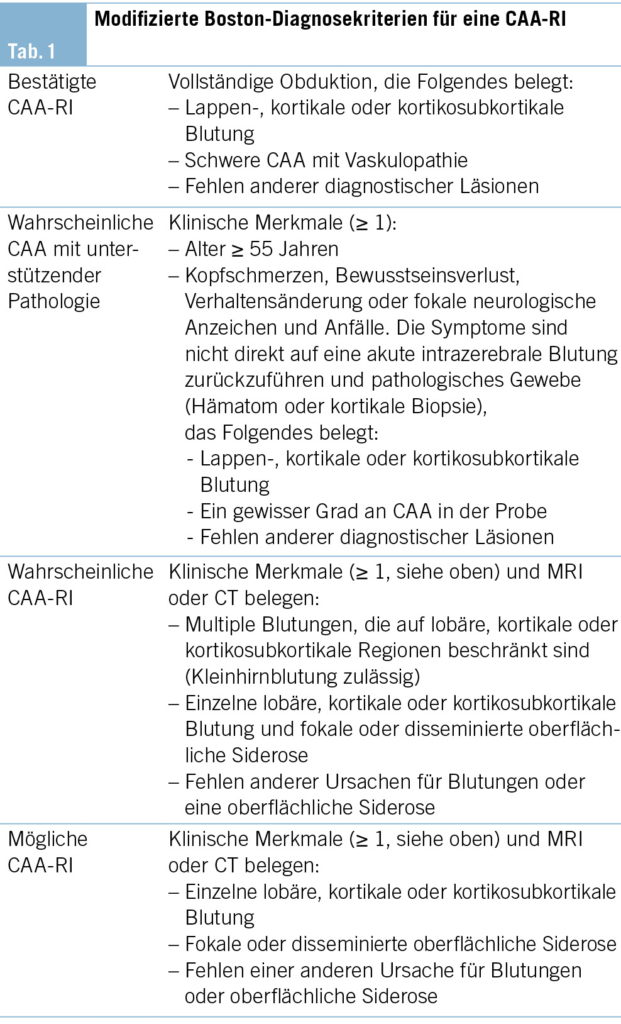

Die Amyloidablagerungen sind bei einem Teil der Patienten mit einer Entzündung der Gefässwand vergesellschaftet, was schliesslich zu einem multifokalen Marklagerödem führt. Insgesamt zeigen diese Veränderungen im MRI ein typisches Bild, welche für die Diagnosestellung einer CAA-RI wesentlich sind. Die Veränderungen lassen sich vor allem in der FLAIR-Sequenz (fluid attenuated inversion recovery) und bei der SWI (Suszeptibilitätsgewichtete Bildgebung) feststellen (2, 3). Dazu gehören Mikroblutungen, eine kortikale superfizielle Siderose und eine asymmetrische fleckförmige oder konfluierende Leukenzephalopathie, welche den angrenzenden Kortex und das subkortikale Marklager miteinbeziehen können. Ebenfalls kann sich als Zeichen der entzündlichen Reaktion ein vasogenes Ödem in der ADC- (apparent diffusion coefficient) Wichtung präsentieren (2, 4, 5). Es wurden die sogenannten modifizierten Boston-Kriterien entwickelt, welche auf eine gute Sensitivität und Spezifität geprüft wurden (6) (Tab. 1) und bei der Diagnosesicherung helfen. Zusätzliche klinische Diagnosekriterien sind ein akuter/subakuter Symptombeginn, Alter über 55 Jahre, Symptome wie Kopfschmerzen, Wesensveränderungen, kognitive Defizite oder fokal neurologische Defizite oder epileptische Anfälle. Andere Ursachen (z. B. infektiös oder paraneoplastisch) müssen ausgeschlossen werden. Sind alle diese Kriterien erfüllt, gilt eine CAA-RI als wahrscheinlich. Zur definitiven Diagnosesicherung wird eine histologische Bestätigung im Rahmen einer Autopsie benötigt, wobei sich neben frischen und alten Ischämien und Einblutungen auch entzündliche, perivaskuläre Veränderungen ohne Gefässbeteiligung finden lassen. Hier kann eine Unterscheidung zur Beta-Amyloid-assoziierten Angiitis (ABRA) gemacht werden, welche ausgeprägtere vaskulitische Veränderungen und fibrinoide Gefässwandnekrosen zeigt. Diese erheblichen Zerstörungen des Hirnparenchyms direkt durch invasive zytotoxische T-Lymphozyten und indirekt durch vaskulitische oder begleitthrombotische Gefässverschlüsse bedingen eine stärkere Immunsuppression als bei der CAA-RI. Teils wird in der Literatur jedoch die ABRA synonym zur CAA-RI genannt. Ob eine Histologie zur Diagnosestellung einer CAA-RI immer zwingend ist, steht aktuell immer noch zur Diskussion. Eine genaue Diagnose hat jedoch teils therapeutische Konsequenzen. Vor allem bei fehlendem Therapieansprechen sollte eine Biopsie angestrebt werden.

• Multiple, auf lobäre, kortikale oder kortikosubkortikale Regionen beschränkte Blutungen im MRI oder der CT des Neurokraniums oder auch in einer Hirnbiopsie erhärten die Verdachtsdiagnose einer CAA-RI.

• Zur Diagnosebestätigung wird eine vollständige Obduktion benötigt.